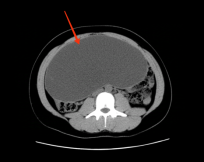

再来看第二张CT图片,这是一位24岁未婚未育女性,一直各种方式减肥,却怎么也瘦不下了肚子,是因为其母亲发现其腹部异常来院检查发现盆腹腔巨大包块,CT提示包块最大横截面约22cm*10cm,来源于卵巢可能;

1.png